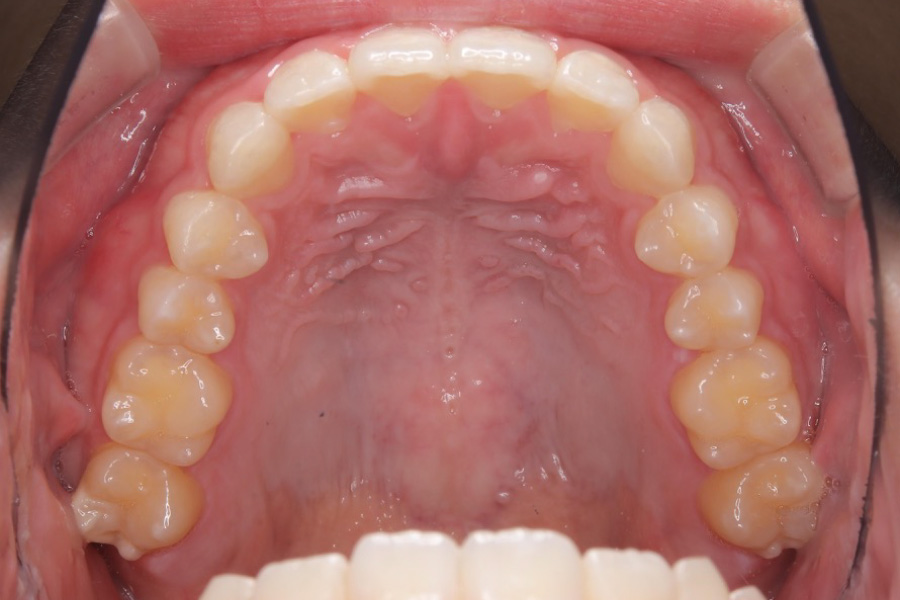

治療後

主訴 歯のガタつき

期間 1年半

治療内容 インビザライン矯正

非抜歯